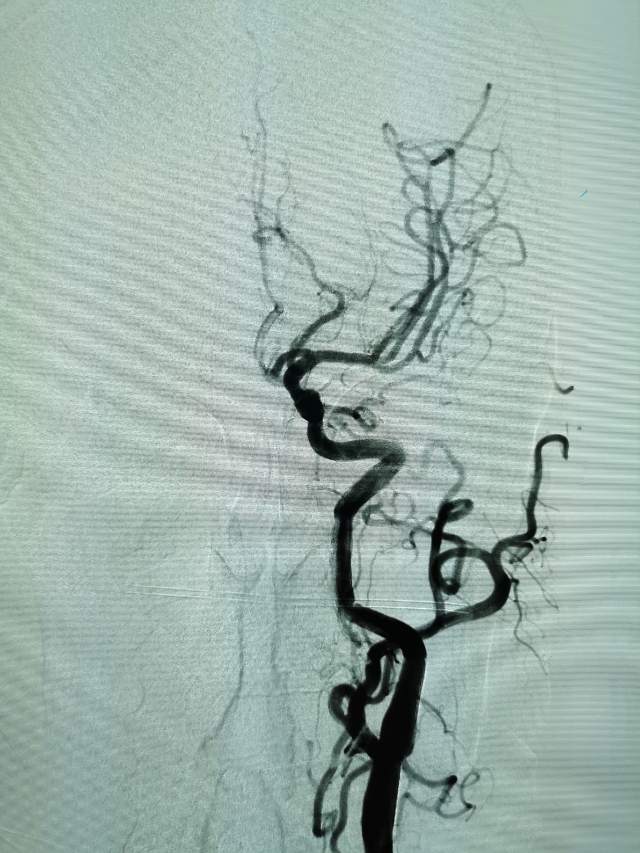

进一步行DSA检查后发现:左侧颈内动脉起始部有一个颈动脉蹼。这个血管内的“蹼”,是一个薄片状的结构,类似掌部的“蹼”,它会在颈内动脉起始部产生“扰流效应”,瘀滞的血流存在栓子形成和脱落的风险………,冲散的栓子可以“天女散花”,也可以“天上掉下石头”,这不,这位兄弟就被掉下的石头砸到颅内的功能区了,手脚语言都砸坏了。